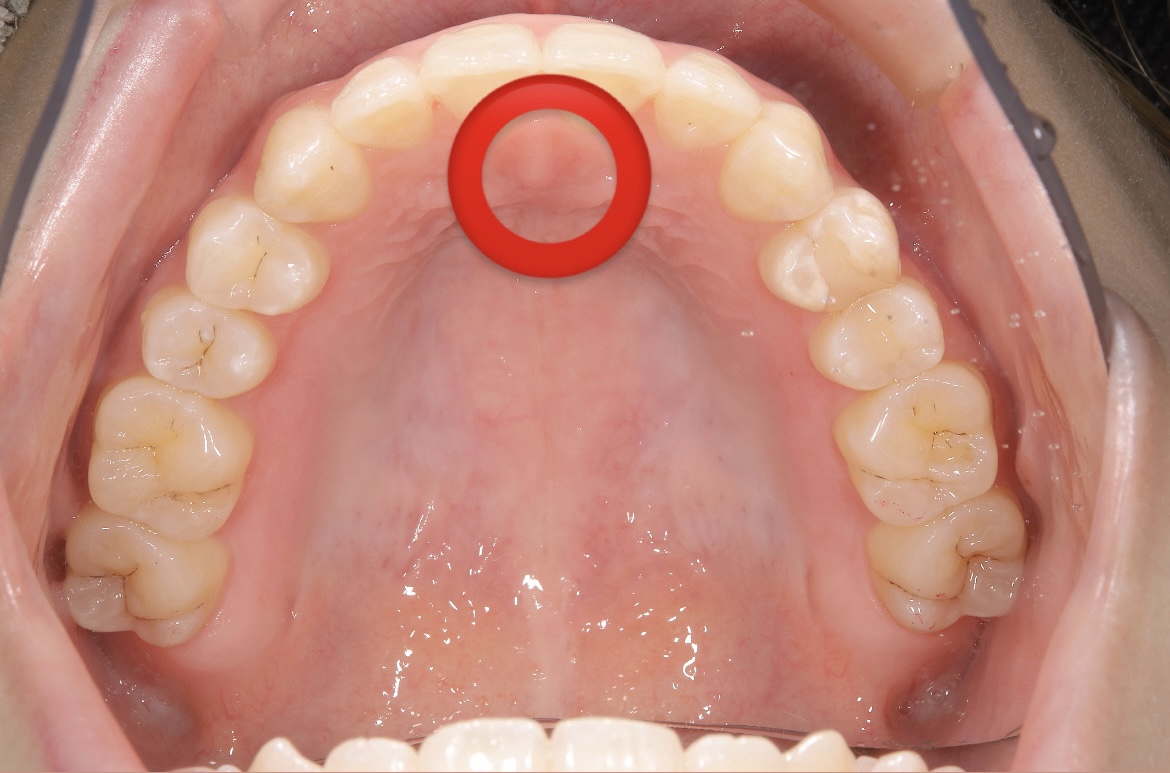

舌は、上顎の前歯の裏にあるスポット(スポットポジション)にあるのが理想です。

1. 舌先を上顎の前歯のすぐ後ろに当てる

2. 舌全体を上顎に吸いつけるように密着させる

3. そのまま鼻で呼吸しながら10秒キープ

4. リラックスして元に戻す

これを1日3回以上行いましょう。

舌の正しい位置を覚えることで、口呼吸が改善され、口元の筋肉が内側に引き寄せられる感覚が出てきます。